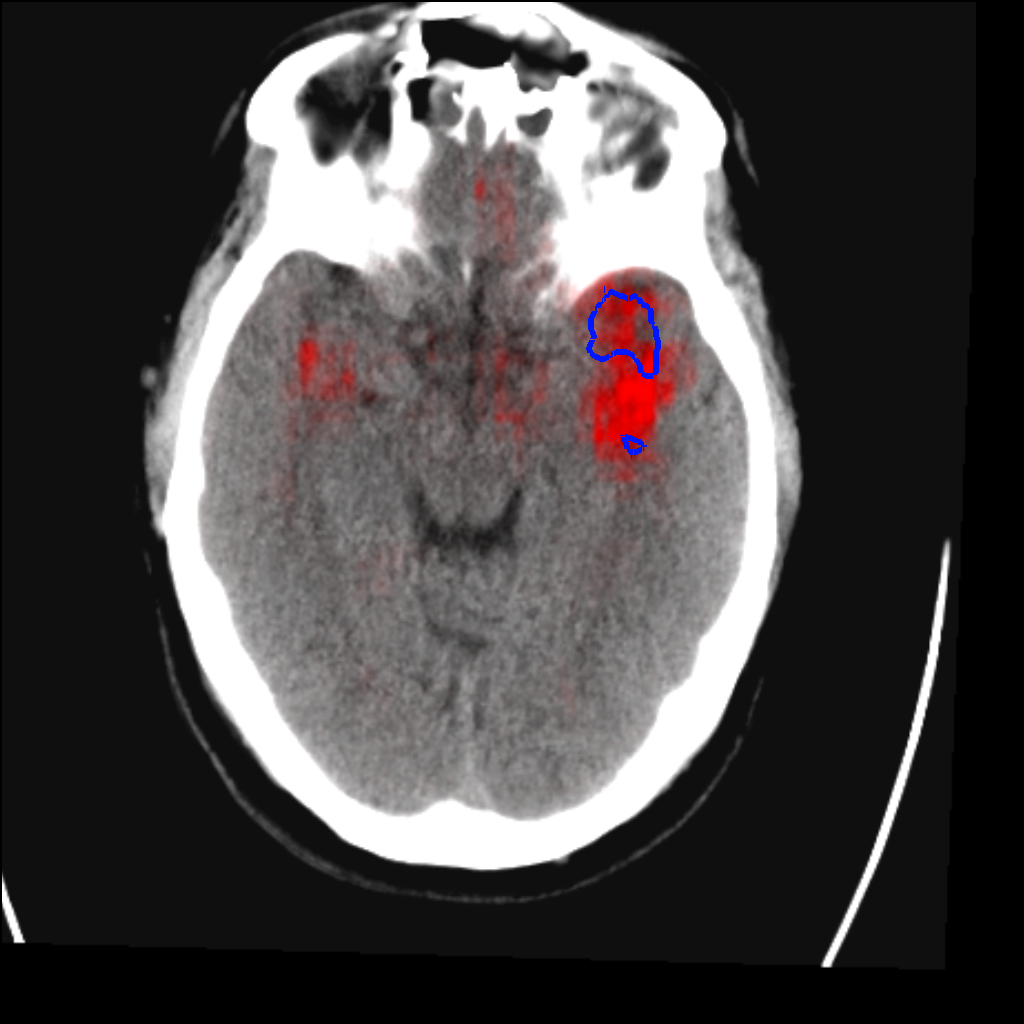

Fig. 3 shows a scatter plot and a Bland-Altman plot of the true and predicted volumes for all subjects in the testing folds using the proposed method. The mean volume error is -2.8 ml (the prediction is a slight underestimation) and the mean absolute volume error is 36.7 ml. The mean Dice score is 0.48. A representative set of predictions is shown in Fig. 4.